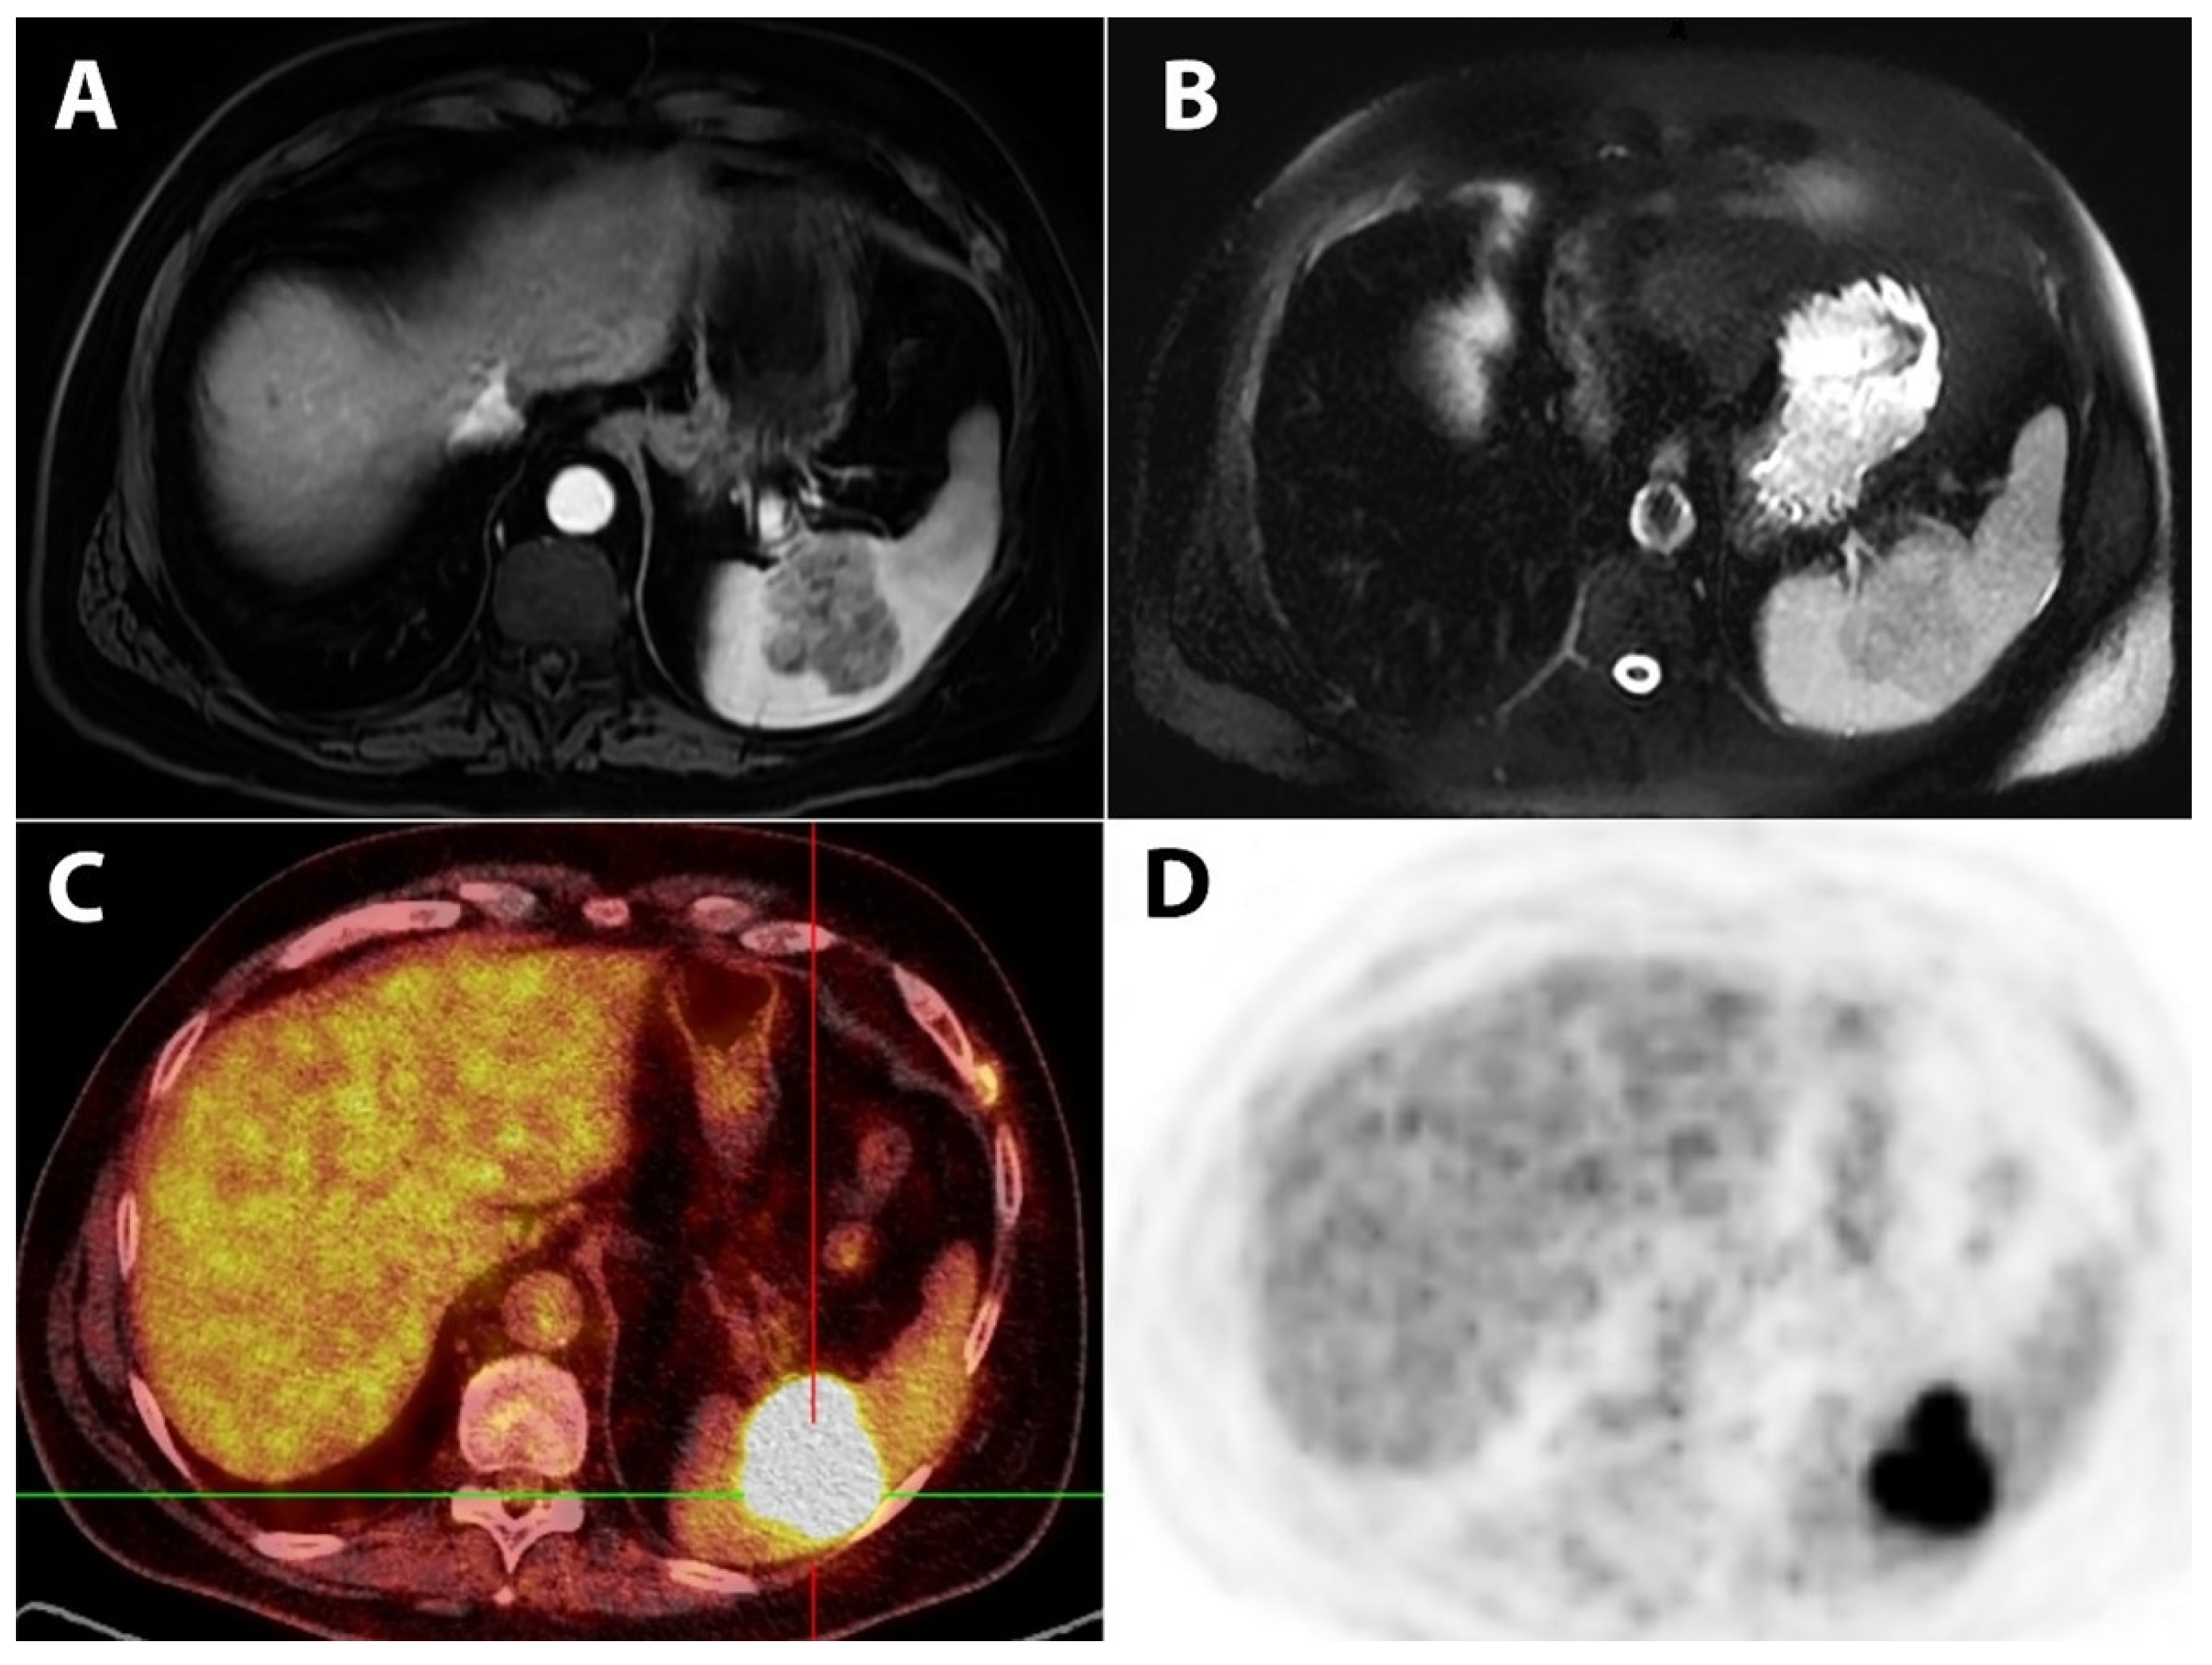

- Soussan, M.; Pop, G.; Ouvrier, M.J.; Neuman, A.; Weinmann, P. Diagnosis of synchronous isolated splenic metastasis from lung adenocarcinoma: Complementary role of FDG PET/CT and diffusion-weighted MRI. Clin. Nucl. Med. 2011, 36, 707–709. [Google Scholar] [CrossRef]